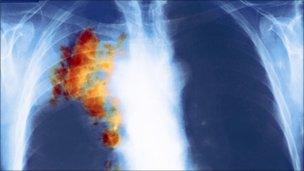

"But it is also clear that too many people are not aware of the symptoms of bowel and lung cancer and are not diagnosed until the disease is in a much more advanced stage, when it is much more difficult to treat."